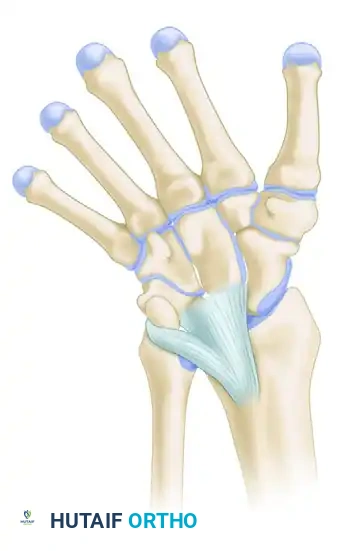

A critical pathoanatomic feature of this condition is the presence of the Vickers ligament—an abnormally thickened, short, and hypertrophic radiolunate ligament. This aberrant ligament creates a dense fibrous tether between the volar-ulnar metaphysis of the radius and the lunate, compressing the volar-ulnar physis and exacerbating the asymmetric growth arrest.

The Vickers ligament is not merely a thickened capsule; it is a distinct, anomalous structure that often contains cartilaginous elements. It originates proximal to the physis on the radial metaphysis and inserts onto the lunate, crossing and compressing the physis. Failure to completely excise this ligament will result in recurrent deformity despite adequate bony bar resection.

3. Identification of the Vickers Ligament

Once the pronator quadratus is reflected, inspect the volar-ulnar aspect of the radius. The Vickers ligament will appear as a thick, white, fibrous band originating from the volar metaphysis, crossing the physis, and inserting deep into the carpus (specifically the lunate).

Identify the abnormal volar ligament tethering the lunate to the radius. Carefully isolate this structure. In patients with extreme volar subluxation of the carpus, the lunate may be severely displaced proximally; take absolute care not to mistake the subluxated lunate for the underlying distal radius metaphysis.

6. Excision of the Vickers Ligament

With the bony bar resected, return your attention to the Vickers ligament. Excise this abnormal tether completely from its metaphyseal origin to its insertion on the lunate. Ensure that the lunate is completely freed from its volar tether to the radius, allowing the carpus the potential to remodel and translate dorsally as the radius grows.

- Incomplete Ligament Release: Failure to completely excise the Vickers ligament will leave a persistent soft-tissue tether, preventing carpal remodeling even if the bony bar is successfully resected.